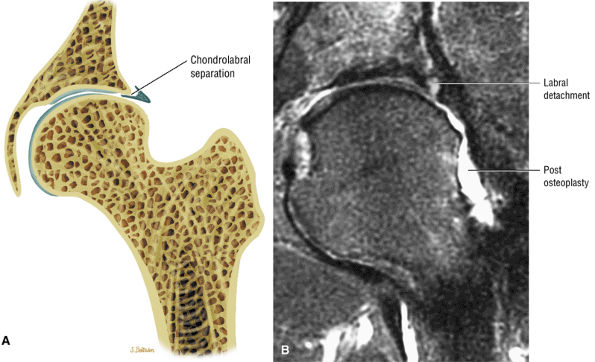

-

Chondral fissures or defects, joint space narrowing, and femoral head edema, seen in the advanced stages of FAI

Thickening of the iliofemoral ligament and synovitis adjacent to the capsule and proximal femur